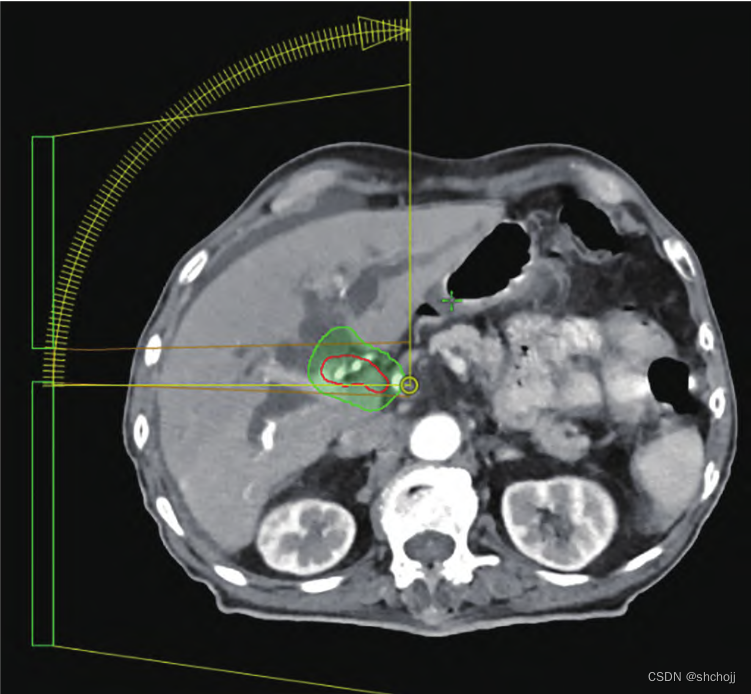

平扫CT(A),迭代算法去除伪影重建CT,实现低剂量扫描同时去除图像金属伪影(B)。需要询问物理师,电子密度是否正确,校正重建图像CT值的偏差是否在剂量计算容许误差范围内。

定位包含高密度造影剂图像(A)、水密度替换(B);原计划(C);原计划复制后,相同射野和机器跳数,出现高剂量红色区域(D)

3、射野(Beam)

-

照射合理:、入射角度、入射数量

入射角度近靶区侧

设置Block(两侧棕色区域)进行剂量约束